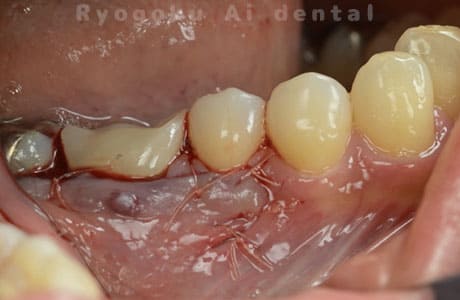

Case05

-

術後2ヶ月

- 原因

- 右下6番近心根パーフォーレーション

- 治療内容

- 外科的パーフォレーションリカバリー治療

- 治療費用

- ¥66,000

右下の奥から2番目の歯に穴が空いており、腫れが引かず、他院で抜歯と診断された患者様です。被せ物を外さずに、穴が空いている部分に外科的にアクセスし、その部分を修復手術を行いました。治療後も再発せず、経過良好です。

<リスク・副作用>

手術後は痛み、腫れ、痺れ、青あざなどの副作用が生じます。痛みは痛み止めを処方しますが、腫れ、青あざは1週間程度生じる場合があります。また、部位によっては神経の走行が複雑で、痺れが残り、長期的にお薬を処方する場合があります。